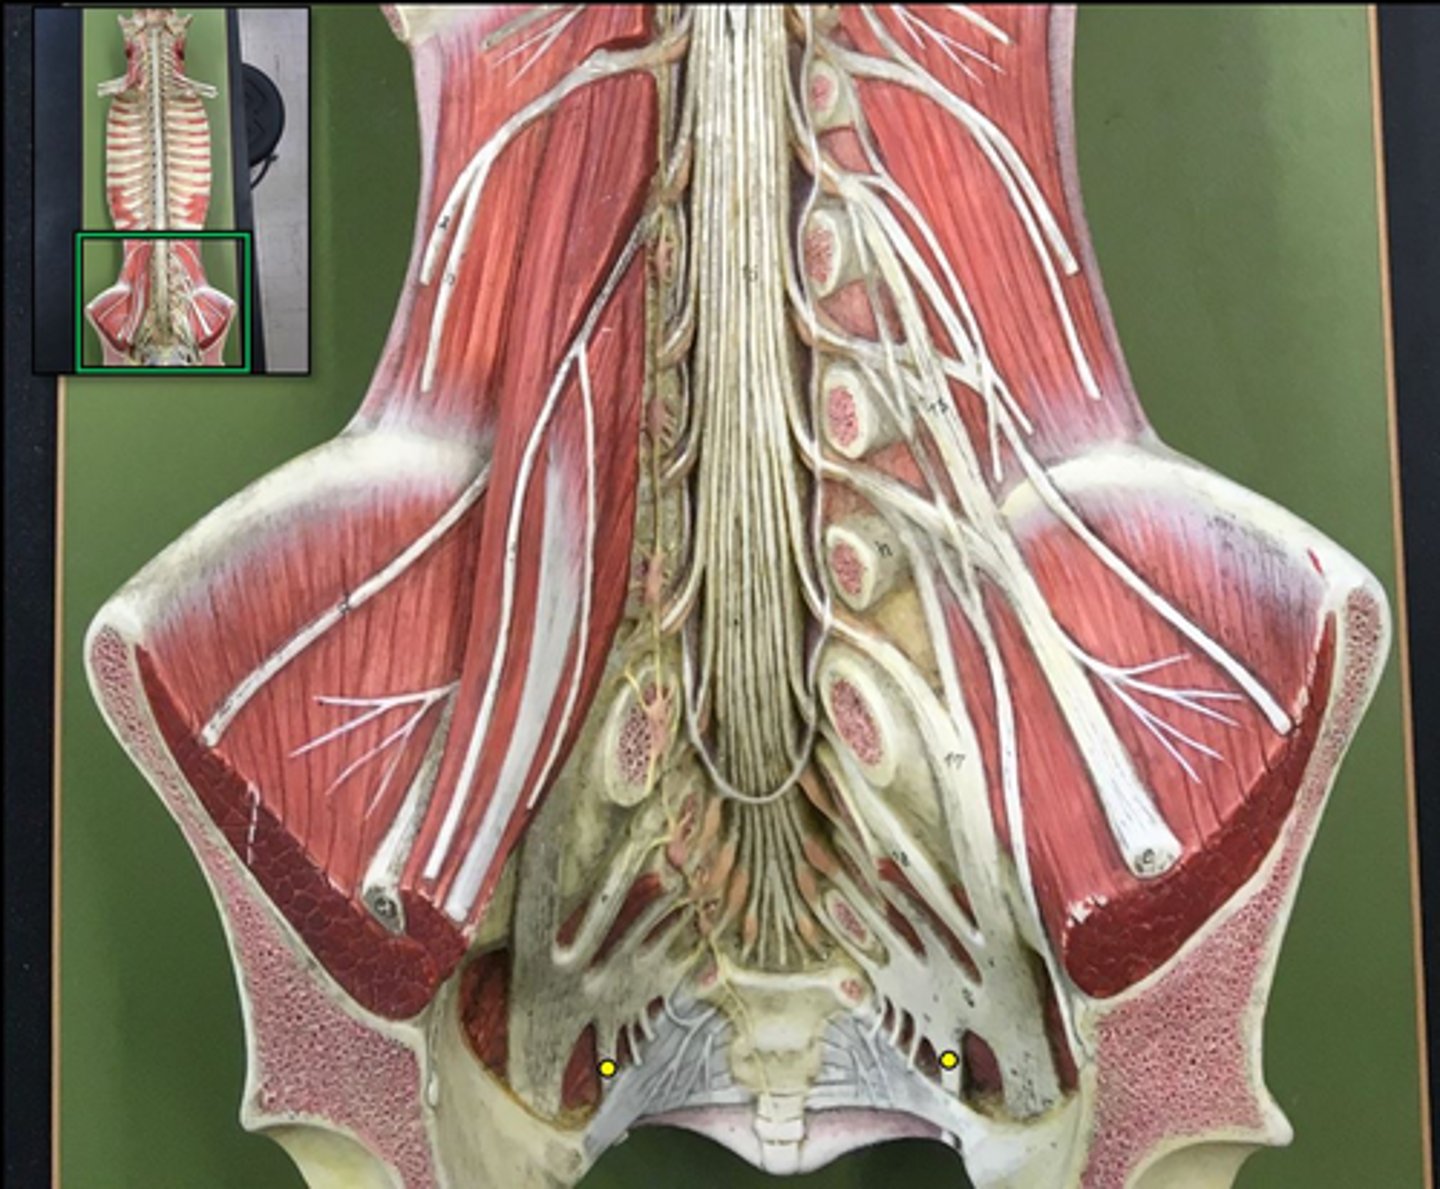

denticulate ligaments

extensions of pia mater that secure cord to dura mater laterally

filum terminale

single thin thread of fibrous tissue at end of conus medullaris in the center that attaches to coccygeal ligament

cauda equina

bundle

sacral plexus

L4- S4

genitofemoral nerve

Wishbone of the leg

lateral femoral cutaneous nerve

femoral nerve

saphenous nerve

posterior femoral cutaneous nerve

sciatic nerve

obturator nerve

common fibular nerve

tibial nerve